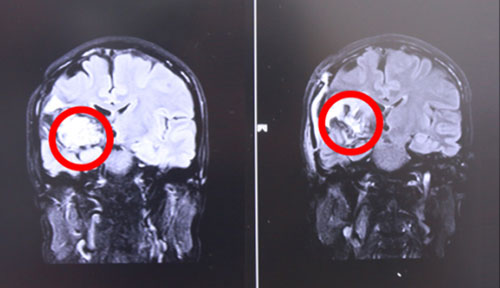

左侧为术前,右侧为术后,术后红圈内肿瘤物基本消失

17号上午9点左右,张XX被推入手术室,在全麻状态下接受“右颞顶海绵状血管瘤切除术”。至手术结束,已经日暮时分。手术由经验丰富的侯增欣主任主刀,上显微镜,分离侧裂,保护血管,切开颞上回皮质,见肿物呈暗褐色,靠近侧裂动脉,并向大脑深部丘脑生长,术中显微镜下肿物近全切除,手术顺利,脑神经及血管保护完好,患者全麻醒,返ICU病房进行术后监护。